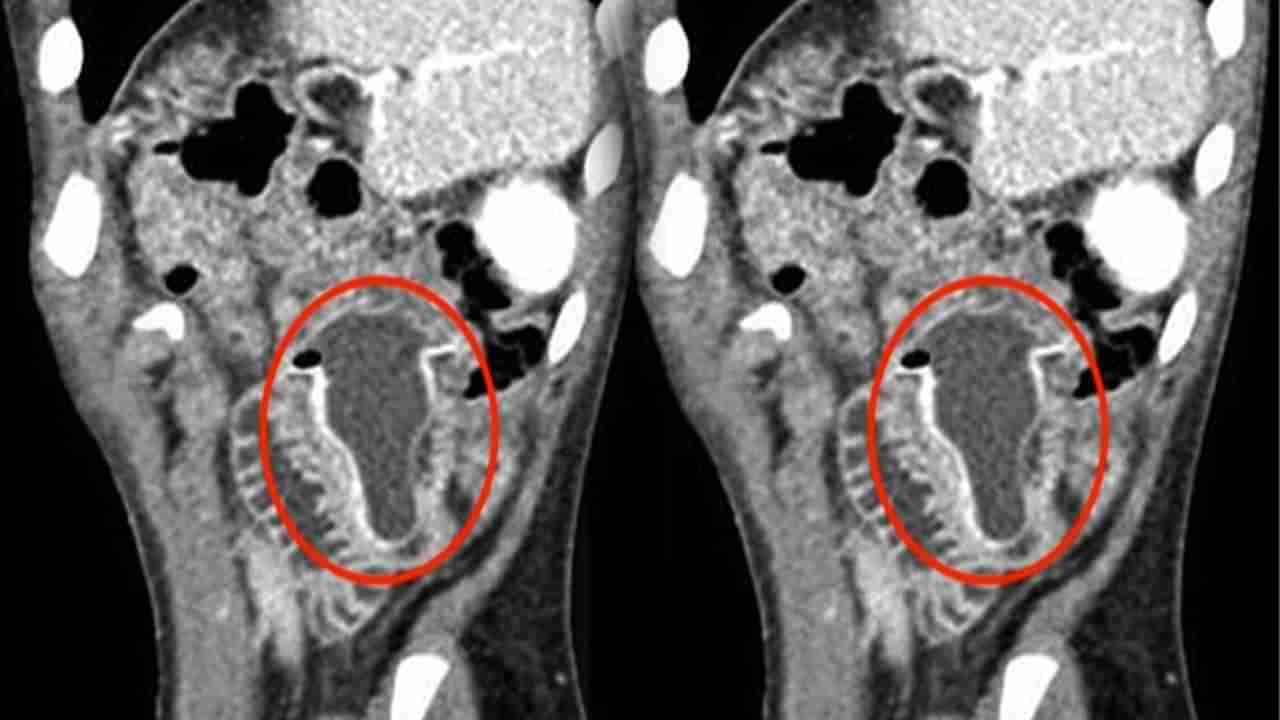

వైద్యులు అతడికి ఎక్స్రే తీయగా.. కడుపులో ఏదో వింత వస్తువు ఉన్నట్టు.. అలాగే అందులో ద్రవం ఉందని గుర్తించారు. ఆపై అది సరిగ్గా చిన్న ప్రేగు మధ్య భాగంలో చిక్కుకున్నట్టు కనుగొన్నారు. అత్యవసర లాపరోస్కోపీ ద్వారా ఆ వస్తువు శరీరంలో సరిగ్గా ఇరుక్కున్న ప్రదేశాన్ని కనిపెట్టారు. శస్త్రచికిత్స ద్వారా దాన్ని తొలగించి కుట్లు వేశారు డాక్టర్లు. ఈ ఘటన సౌదీ అరేబియాలో చోటు చేసుకోగా.. ఆ బాలుడు ఆపరేషన్ అనంతరం ఐదు రోజులకు డిశ్చార్జ్ అయ్యాడు. ఆ తర్వాత మానసిక నిపుణుల పర్యవేక్షణలో కొద్దిరోజులు ఉన్నాడు.